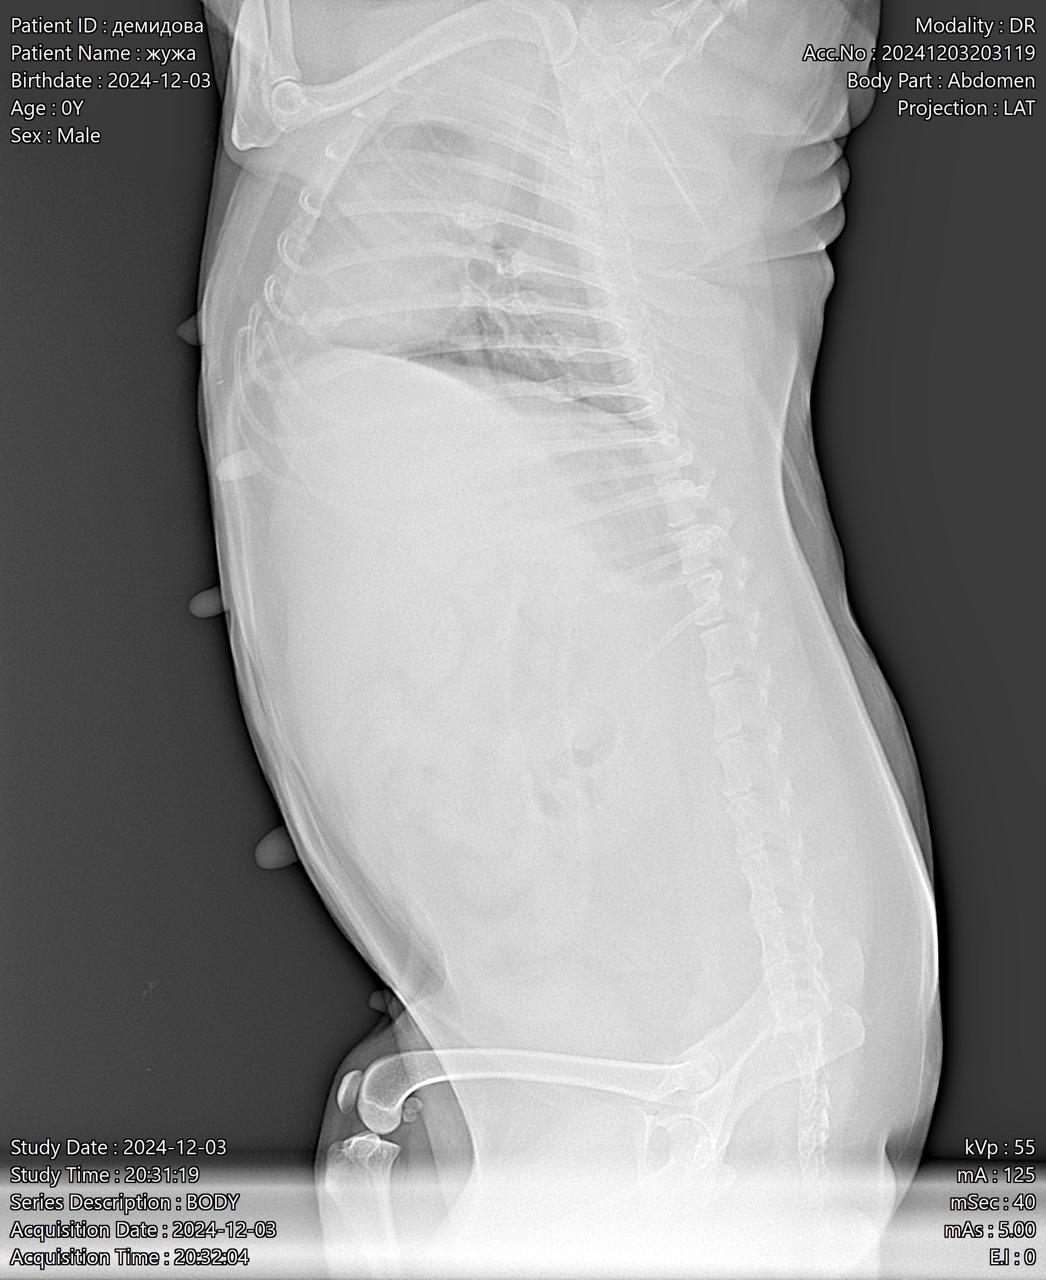

Москва, цверг Жужа, 7 лет

Визит к врачу с поносом